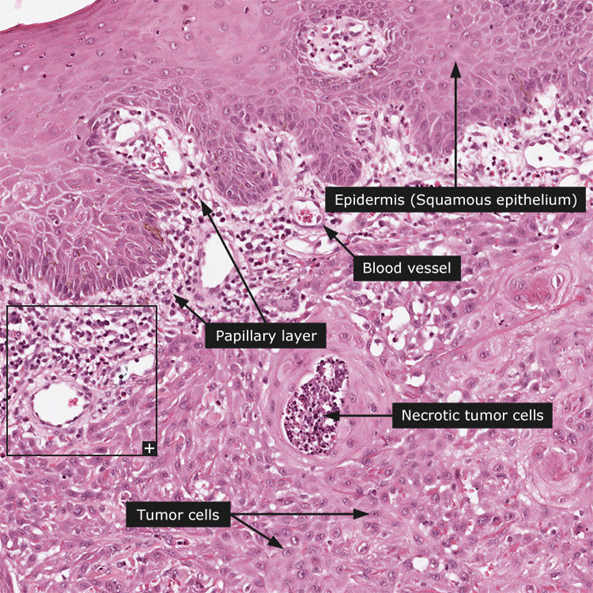

Examination Of Non-Melanoma

Signs Of Squamous Cell Carcinoma